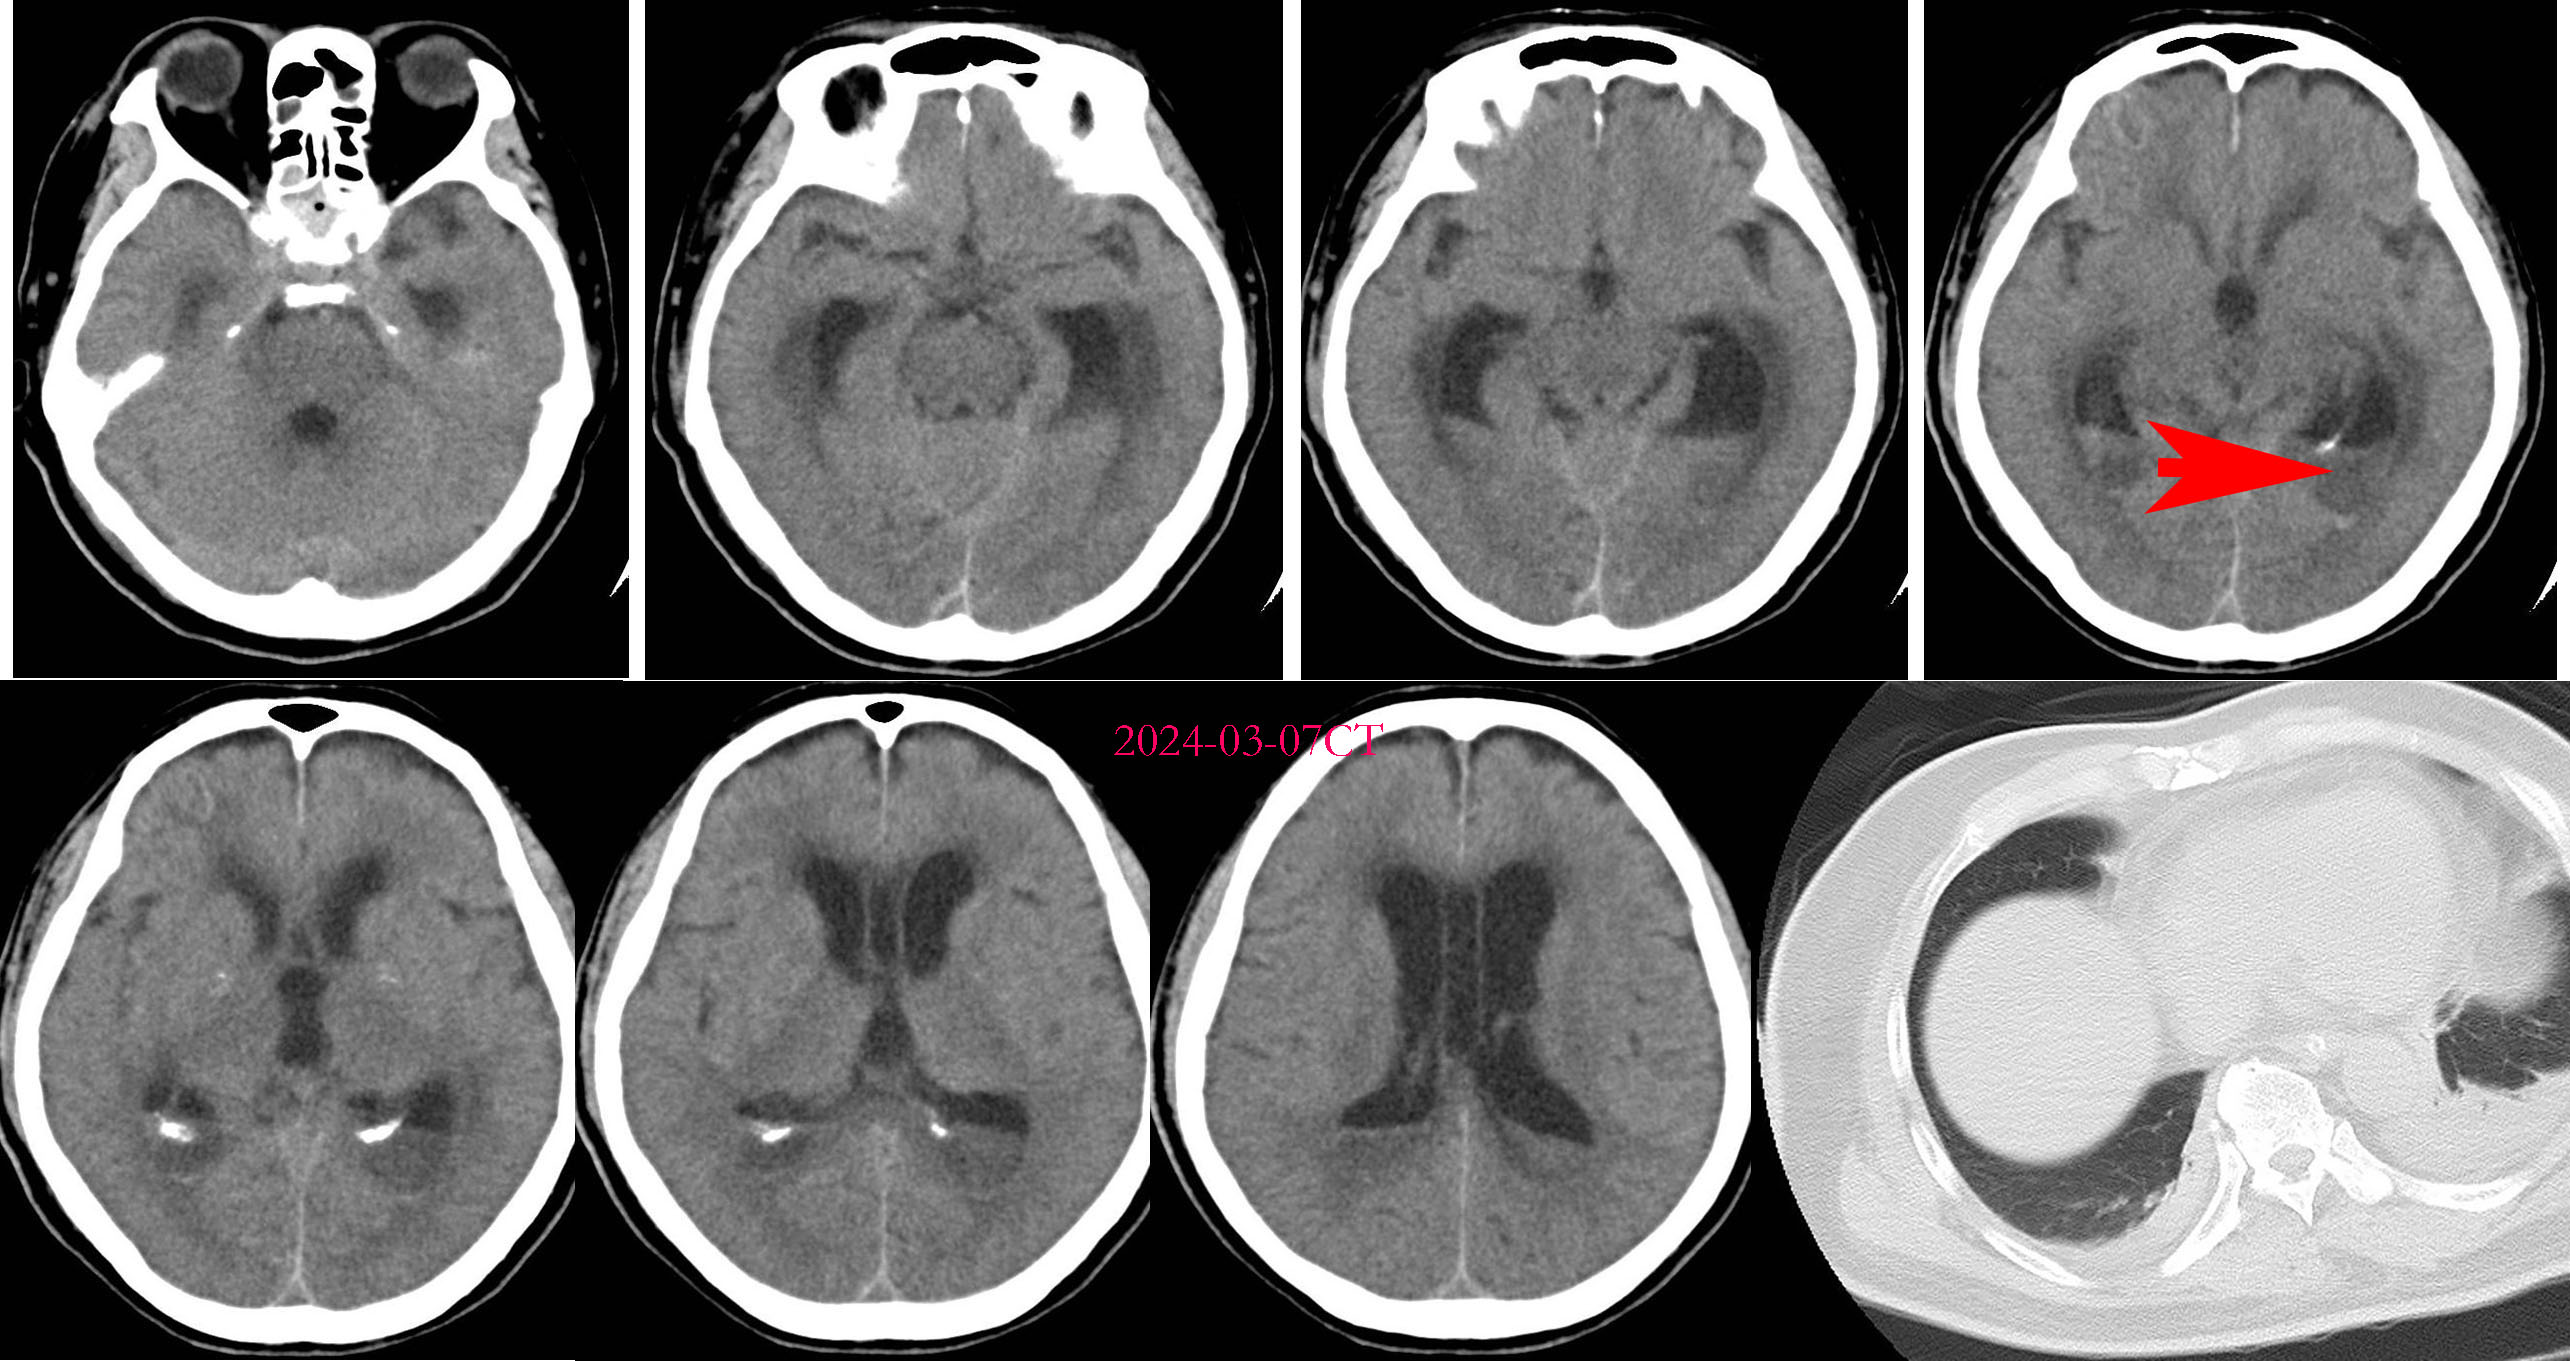

2024-03-07CT复查可见脑室内液平面(下图红色箭头所示),考虑脑脓肿,但患者此时感染性休克,两种升压药物维持血压,凝血障碍,予以纠正。

2024-03-10出现双侧瞳孔散大,直径4.5mm,但神志反应较前好转,刺痛睁眼,刺痛定位。呼吸机通气,升压药已停 。复查CT可见脑室扩大,脑积水,脑室内液平更明显(见下图红色箭头) 急诊全麻下行右额开颅脑内脓肿清除术+三脑室底造瘘术+侧脑室透明隔造瘘术+脑室钻孔外引流术。

急诊全麻下行右额开颅脑内脓肿清除术+三脑室底造瘘术+侧脑室透明隔造瘘术+脑室钻孔外引流术。